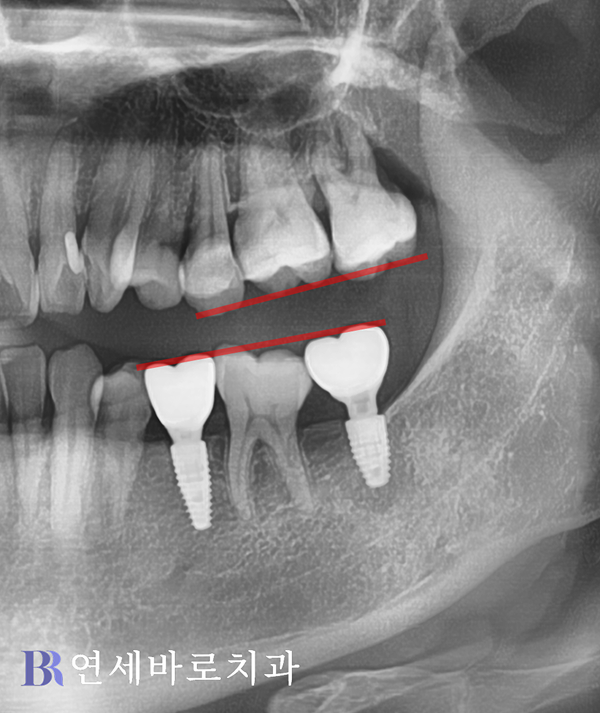

위 사진은 최종 크라운까지

완전히 결합하고 촬영했는데요.

골유착이 잘 이루어진 데다,

교합도 훌륭하게 맞춰졌습니다.

더불어 기존 치아의 삭제 없이

임플란트가 훨씬 안전하게

완성되었다는 점에서 환자분도

긍정적으로 평가하셨습니다.